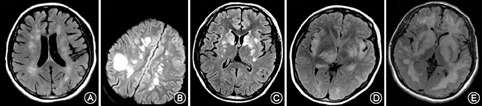

国内外ADEM颅内病灶没有统一分类标准,综合国外文献报道[4,5],主要存在五种表现(图1):(1)散在型:小病灶(<5 mm)散在分布于大脑半球;(2)巨大型:大病灶、融合或瘤样病灶,伴病灶周围水肿和占位效应;(3)基底节型:仅累及双侧基底节区、对称性分布;(4)出血型:在急性脱髓鞘病灶中有出血表现;(5)满天星型:病灶广泛分布,主要局限于白质,呈环状强化。

44例患者中,头颅MRI表现为散在型18例(41%),巨大型10例(23%),基底节型12例(27%),出血型1例(2%),满天星型3例(7%)。33例(75%)出现丘脑及基底节区病灶。22例(50%)存在增强病灶,其中片状强化3例(7%),结节状强化14例(32%),线样强化5例(11%)。29例行脊髓MRI检查,其中14例(48%)存在脊髓病灶。

ADEM患者MRI上病灶数目、分布以及大小均可出现较大变化。Tenembaum等[4]将ADEM病灶分为四种类型,对84例患者随访发现,62%患者表现为散在型,24%为巨大型,12%为基底节型,2%出现出血型病灶。本研究得出类似结论,发现MS样散在型病灶最常见(41%),以丘脑受累为主的基底节型其次(27%),巨大型占一定比例(23%)。此外,Otten等[5]报道了满天星样病灶,该类病灶特点为多发T2病灶,伴环状强化,广泛分布但主要局限于白质,少数有脑干受累。本研究中,满天星型病灶占7%,提示该类型并不罕见。